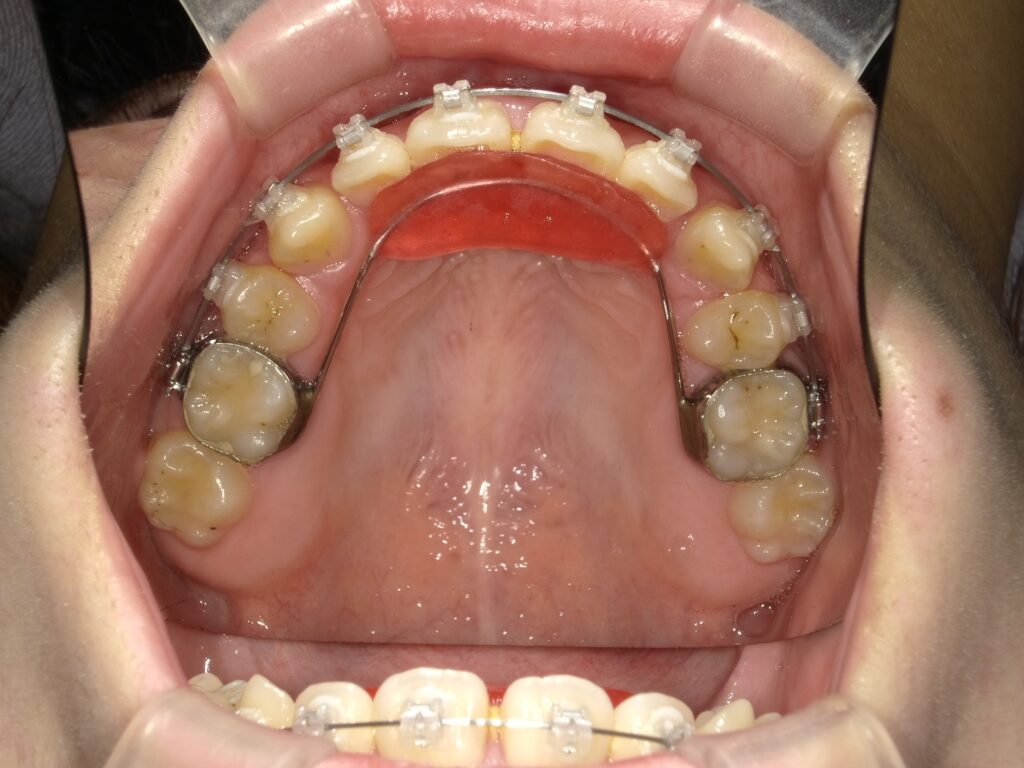

【ブラケット治療】

噛み合わせを正していくために、上前歯裏にバイトプレートという装置を付けました。

これは噛み合わせや顎の問題を改善するために使われます。